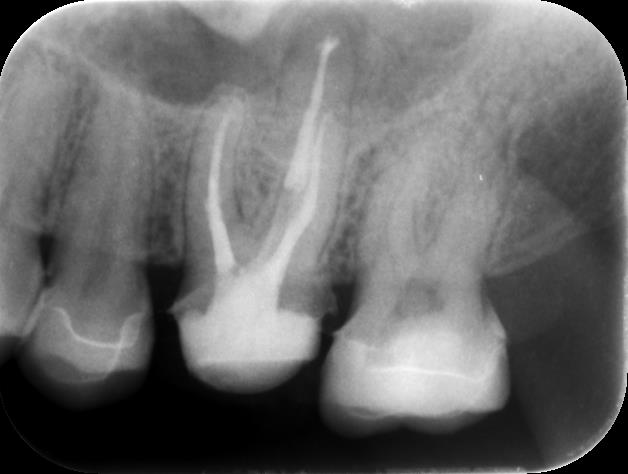

まずはレントゲン写真と口腔内写真をご覧下さい

今回の部位は左上6番です

レントゲン写真、CTでも見てみましょう

黄色く囲っているところはカリエスで、青く囲っているところは根尖病変ができてしまっているところです。

上の歯は上顎洞といって鼻に繋がる空洞があるのですが、今回の歯はその上顎洞の粘膜まで肥厚してしまっています。

治療後のデンタル写真がこちらです。